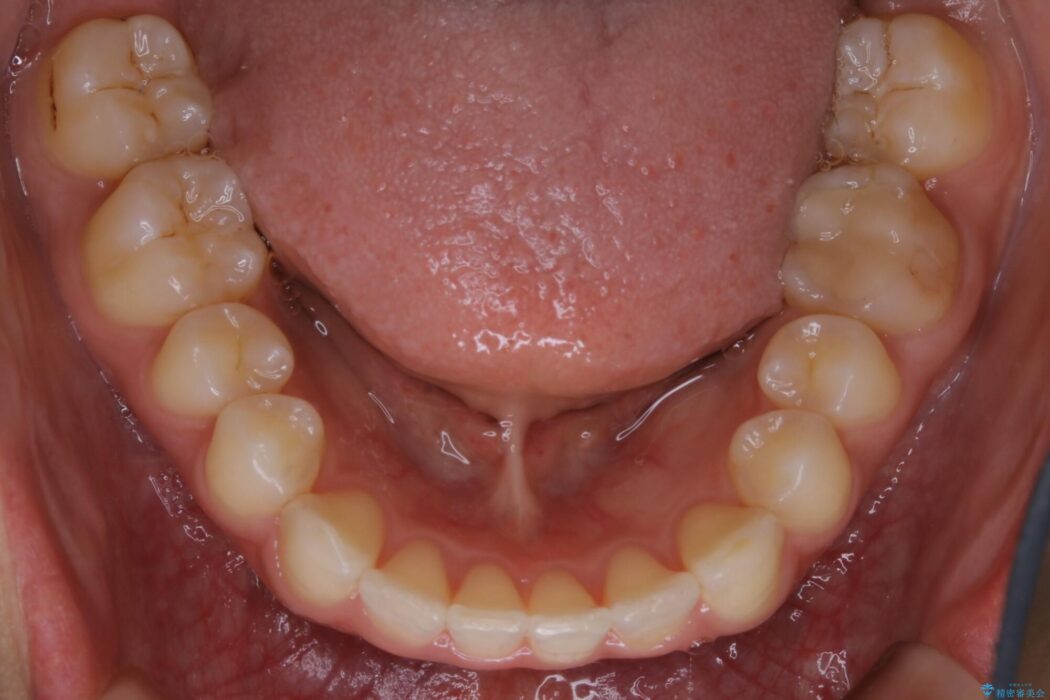

下顎前歯のガタつきを気にされて来院されました。

叢生の度合いにより抜歯は不要と判断しましたので、歯列幅の拡大を主軸に置き矯正治療を行いました。

本症例では下顎の歯列が舌側へ傾くことにより幅が狭まっていましたので、マウスピース治療により歯列弓を拡大しました。